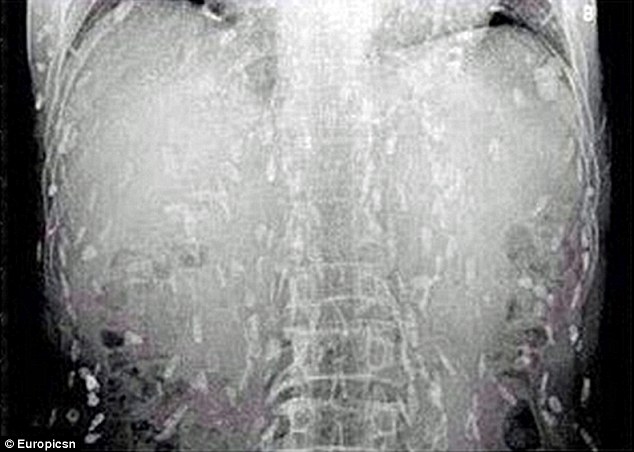

Hình ảnh cho thấy cơ thể của người đàn ông ghiền sashimi đã nhiễm sán dây

Sau những cơn đau dạ dày và ngứa da, anh đã đến bác sĩ để khám. Thật kinh hoàng khi hình ảnh chụp được cho thấy, toàn bộ cơ thể của anh đã bị nhiễm sán dây sau khi ăn quá nhiều sashimi.

Hình ảnh chụp cơ thể của người đàn ông Trung Quốc bị nhiễm sắn dây